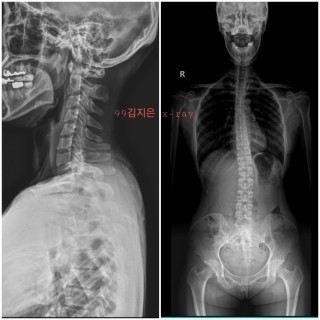

X-ray 촬영.

그 전에 병원에서도 몇 번 찍었었는데, 나의 엑스레이 사진을 이렇게 꼼꼼히 본것은 처음이었습니다. 나름 운동을 해왔었기 때문에 기대를 했었는지, 엑스레이의 비뚤어진 모습은 충격적이었습니다.

목은 일자도 아닌 역C자,그 아래로 휘어진 척추.

그래도 이게 좋아진걸텐데.. 그 전에 엑스레이를 찍어두지 않았던게 너무 아쉬웠습니다.

100일수련의 목표 : X-ray 사진을 예쁘게 만들자.